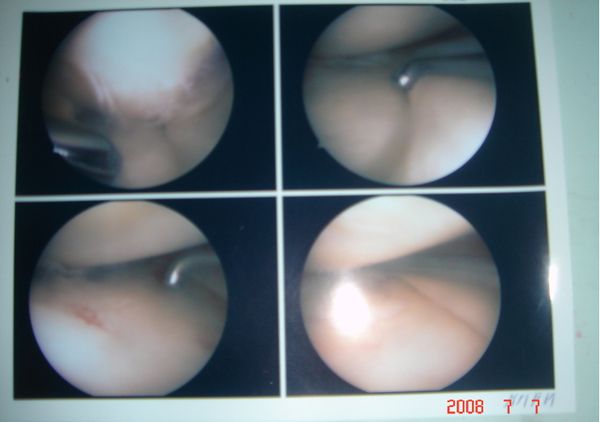

관절내시경 사진